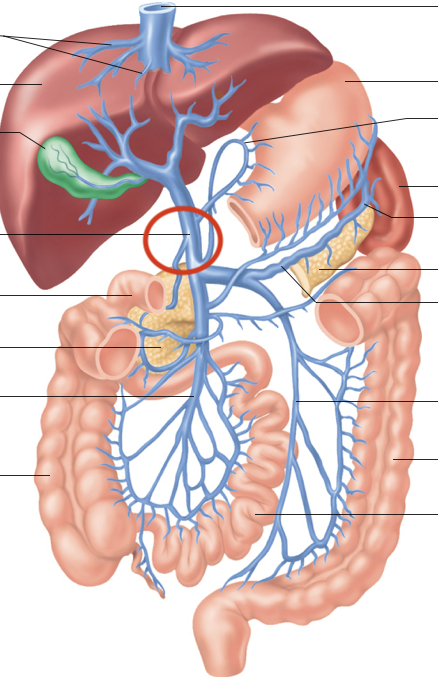

Hepatic Portal System (illustration)

hepatic portal vein

superior mesenteric-small intestine, first half colon

gastric-stomach

splenic-spleen and pancreas

inferior mesenteric-second half colon

hepatic veins